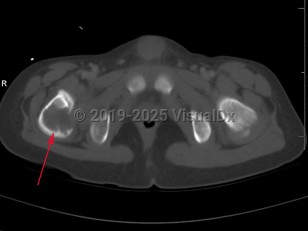

Eosinophilic granuloma of bone in Adult

Langerhans cell histiocytosis (LCH) refers to a spectrum of diseases that includes eosinophilic granuloma (EG), Hand-Schuller-Christian disease, and Letterer-Siwe disease. EG is a rare (seen in 1-5 per million), benign tumor-like disorder that features clonal proliferation of Langerhans cells (antigen-presenting mononuclear cells of dendritic origin) usually found in bones; however, this can involve other organ systems. EG occurs most often in children aged 5-15 years, with a male-to-female ratio of 2:1. EG constitutes 60%-80% of cases of LCH and accounts for less than 1% of all bone tumors. Ninety percent of cases involve a single lesion, usually in the axial skeleton, with just under 10% of cases involving lesions in multiple bones or lesions in other organ systems (ie, skin, pituitary gland, gastrointestinal [GI] tract, lung, spleen, or brain).

The clinical presentation of EG depends largely on the location affected. EG is most often confined to the axial skeleton. EGs are often asymptomatic and found incidentally, or may initially present with pain and swelling of the affected area, with or without decreased range of motion. Commonly affected areas of the skeleton include (in order of frequency): skull, femur, pelvis, mandible, clavicle, ribs, and long bones (of the diaphysis and metaphysis).